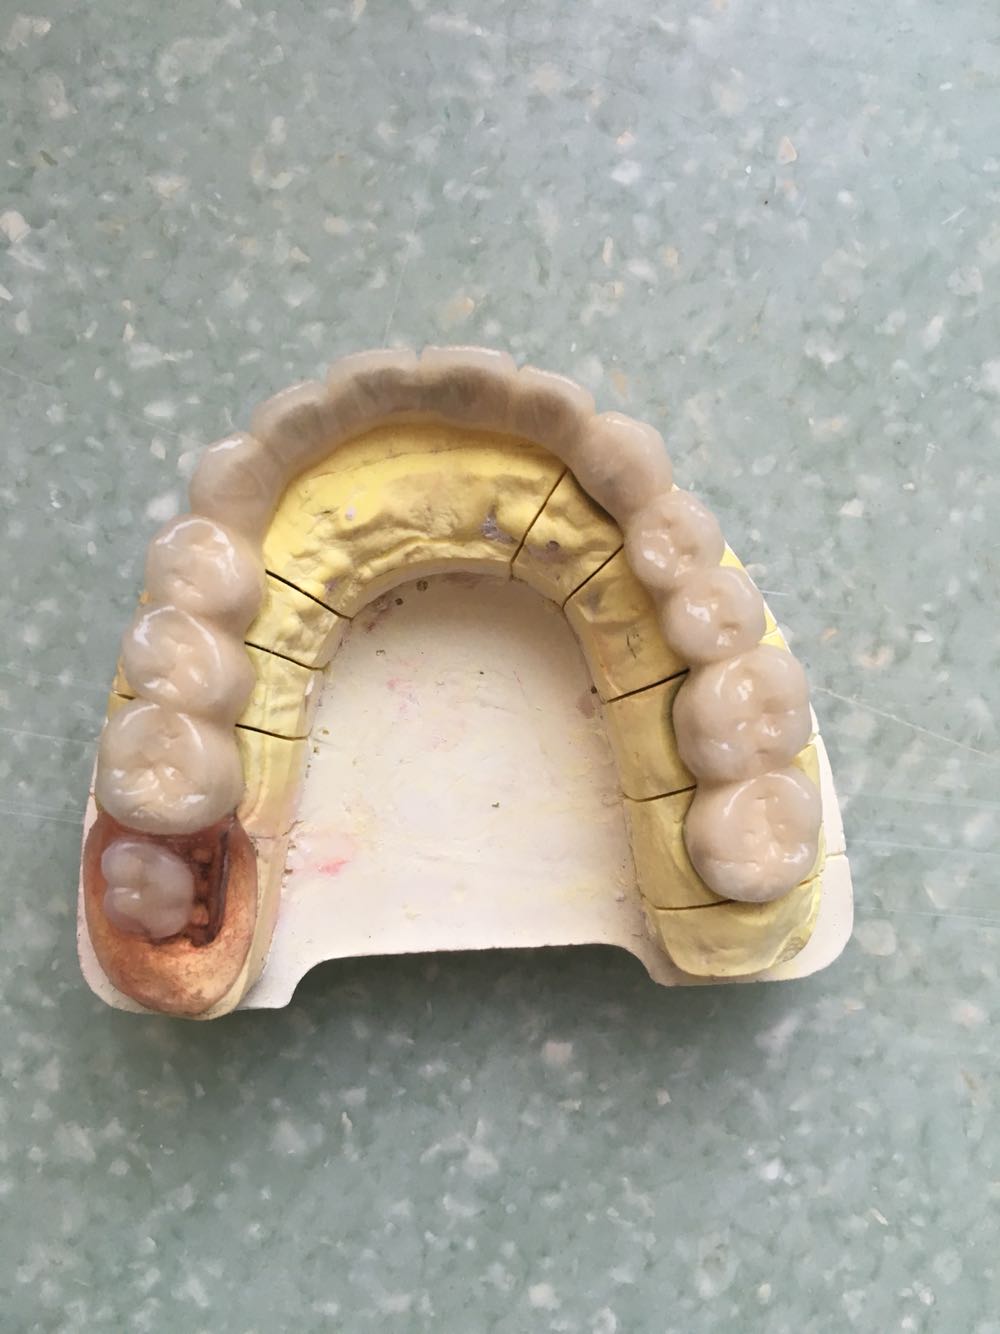

查体:11,12,13,17,21,22,24,25缺失牙槽嵴愈合好,14,15,16,23,26,27牙齿不同程度龋坏,下颌牙齿正常,部分牙齿伸长。

诊断:上颌牙列缺损, 治疗:下颌伸长牙齿调磨,口内上颌牙齿完善根管治疗,行套筒冠修复

随访:一次性试戴成功,咬合好,龈缘密合,定期口腔检查,嘱做好牙周维护。 讨论:套筒冠的适应症及制作技巧